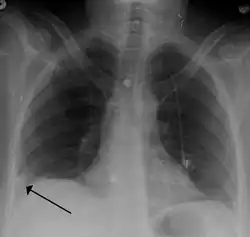

Low probability diagnostic tests/non-diagnostic tests

Tests that are frequently done that are not sensitive for PE, but can be diagnostic.

• Chest X-rays are often done on people with shortness of breath to help rule out other causes, such as congestive heart failure and rib fracture. Chest X-rays in PE are rarely normal,[70] but usually lack signs that suggest the diagnosis of PE (for example, Westermark sign, Hampton's hump).